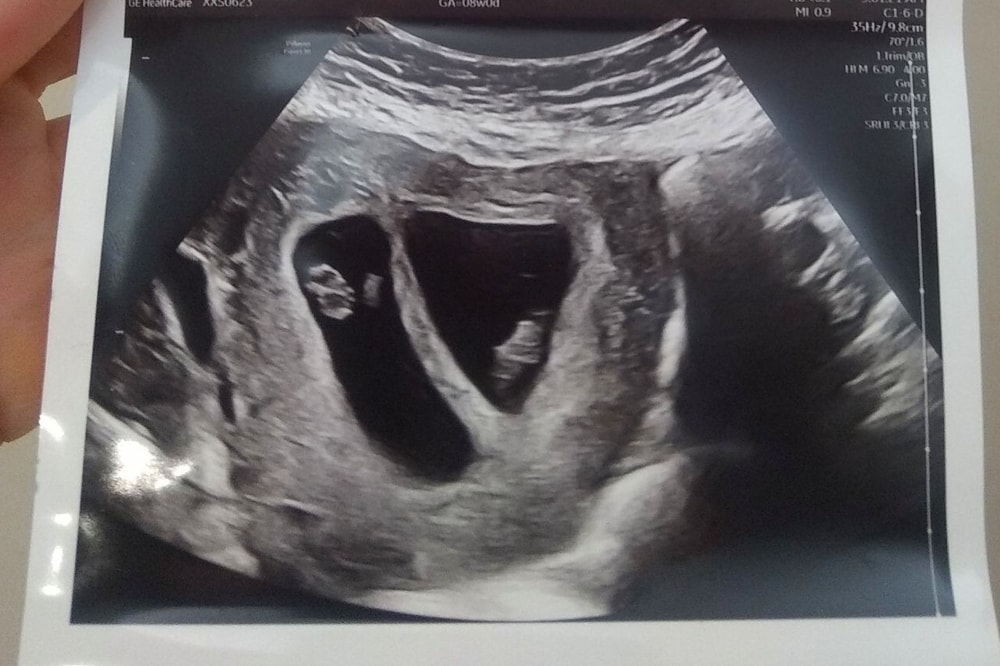

Вот моё УЗИ на 8 недели, ди-ди, мальчик и девочка Изображение

Лёля, О, спасибо! На моих похоже!

Мне кажется, что разнояйцевые. У однояйцевых картина чуть другая